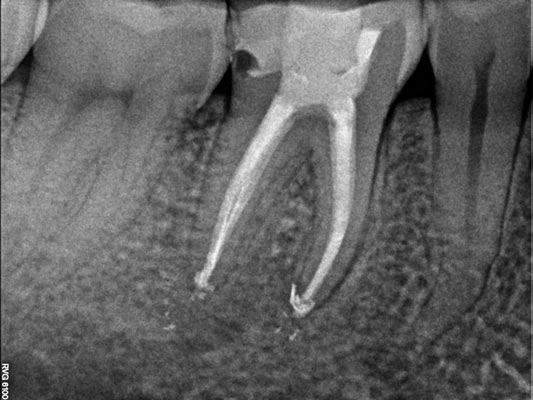

En los casos en los que una endodoncia previa no ha tenido el resultado esperado, es posible realizar una reendodoncia. Este procedimiento consiste en retirar el material de relleno anterior, localizar y tratar conductos que no fueron tratados inicialmente y aplicar un protocolo de desinfección riguroso antes de volver a sellar correctamente todo el sistema de conductos. La reendodoncia permite resolver infecciones persistentes y, en muchos casos, evitar la extracción, conservando el diente natural y mejorando su pronóstico a largo plazo.

Imágenes: Reendodoncia en un molar inferior derecho